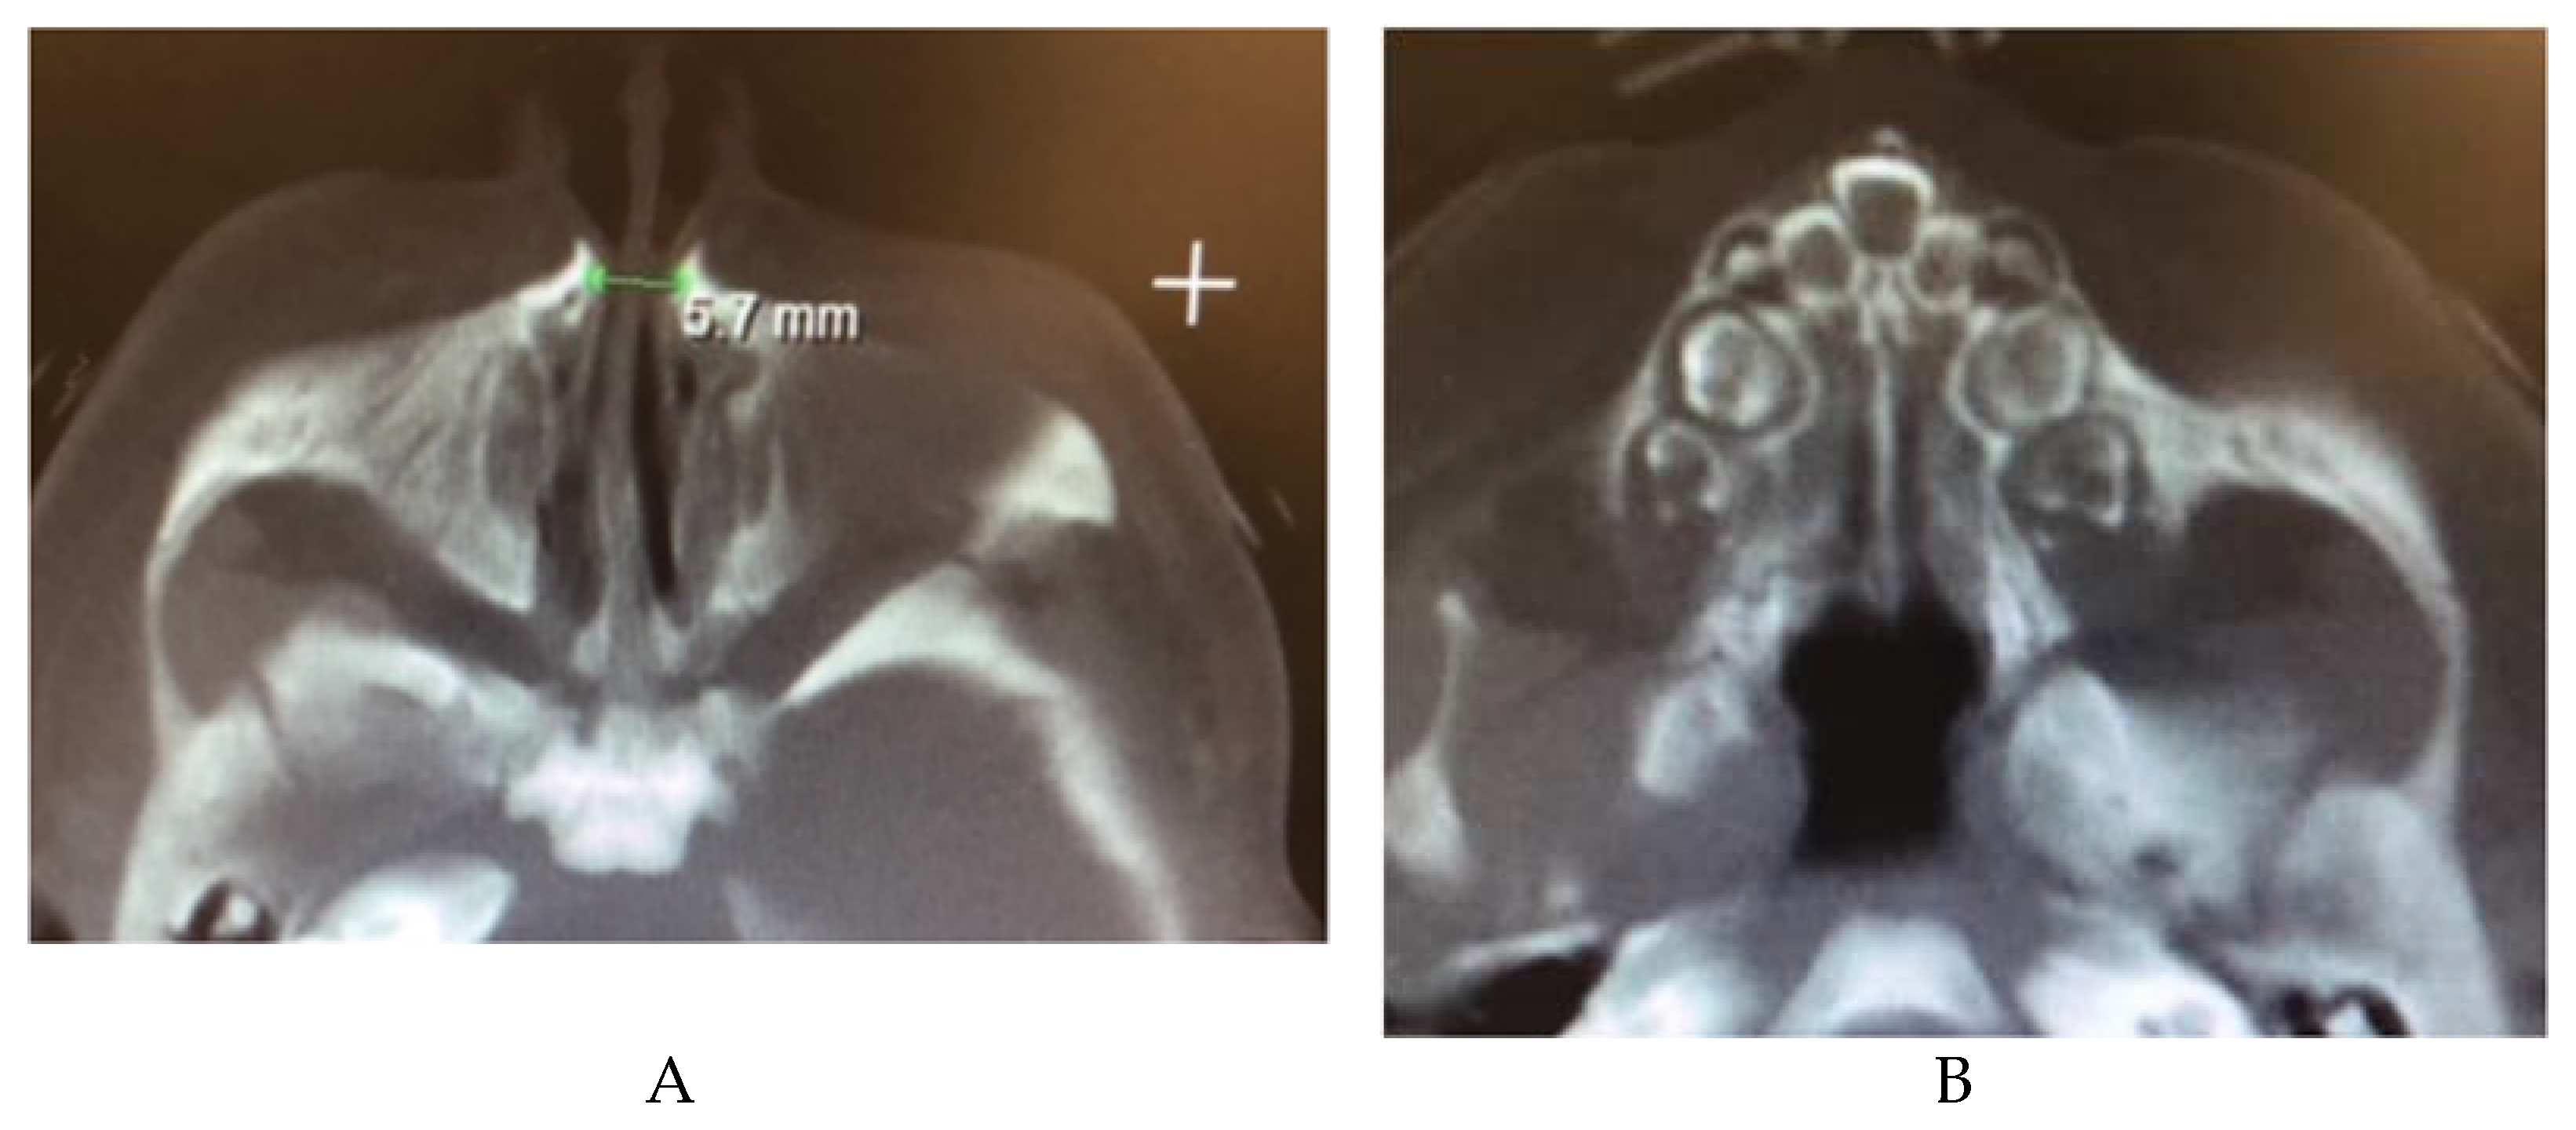

2.12.1. Congenital Nasal Pyriform Aperture Stenosis

- Brown, O.E.; Myer, C.M., 3rd; Manning, S.C. Congenital nasal pyriform aperture stenosis. Laryngoscope 1989, 99, 86–91. [Google Scholar] [CrossRef]

- Guilmin-Crepon, S.; Garel, C.; Baumann, C.; Bremond-Gignac, D.; Bailleul-Forestier, I.; Magnier, S.; Castanet, M.; Czernichow, P.; van den Abbeele, T.; Leger, J. High proportion of pituitary abnormalities and other congenital defects in children with congenital nasal pyriform aperture stenosis. Pediatr. Res. 2006, 60, 478–484. [Google Scholar] [CrossRef] [Green Version]

- Shah, G.B.; Ordemann, A.; Daram, S.; Roman, E.; Booth, T.; Johnson, R.; Xi, Y.; Mitchell, R. Congenital nasal pyriform aperture stenosis: Analysis of twenty cases at a single institution. Int. J. Pediatr. Otorhinolaryngol. 2019, 126, 109608. [Google Scholar] [CrossRef]

- Sesenna, E.; Leporati, M.; Brevi, B.; Oretti, G.; Ferri, A. Congenital nasal pyriform aperture stenosis: Diagnosis and management. Ital. J. Pediatr. 2012, 38, 28. [Google Scholar] [CrossRef] [PubMed] [Green Version]

- Losken, A.; Burstein, F.D.; Williams, J.K. Congenital nasal pyriform aperture stenosis: Diagnosis and treatment. Plast. Reconstr. Surg. 2002, 109, 1506–1511, discussion 1512. [Google Scholar] [CrossRef] [PubMed]